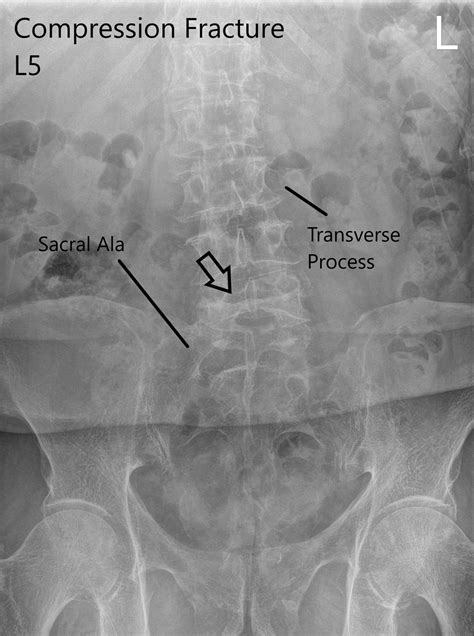

First off, what are we even talking about when we say ‘L1 compression fracture’? L1 refers to the first lumbar vertebra, which is a bone in your lower back. A compression fracture happens when a vertebra collapses, usually due to weakened bone. Think of it like a building where the bricks start to crumble under pressure. This type of fracture is super common, especially in older adults, and is often associated with osteoporosis, a condition that makes bones brittle. However, it can also occur due to trauma, tumors, or other underlying medical conditions. The pain associated with an L1 compression fracture can range from mild to severe, often described as a sharp, stabbing pain that worsens with movement, standing, or sitting. Some people might even experience pain that radiates to other parts of their body. It’s a pretty big deal for someone’s mobility and quality of life, guys, so getting the diagnosis and coding right is absolutely paramount. We need to be precise because it directly impacts treatment plans, insurance claims, and statistical tracking of these injuries.

Alright, let’s get to the nitty-gritty: the ICD-10 code for an L1 compression fracture . Based on the ICD-10-CM guidelines, a compression fracture of the L1 vertebra typically falls under the category of ‘Fracture of vertebra’. The specific code you’ll most commonly use is S22.041A . Let’s break this code down: ’S’ indicates an injury. ‘22’ points to fractures of the thoracic and lumbar spine. ‘04’ specifies a vertebral fracture, ‘L1’. And the ‘1’ signifies the right side, though for a general compression fracture without specific laterality indicated, ‘1’ is often used by default or the provider will specify. The ‘A’ at the end denotes the initial encounter for a closed fracture . This is super important because the code changes depending on whether it’s the first time the patient is being seen for this fracture (initial encounter), if they are receiving routine healing care (subsequent encounter), or if it’s a late effect of the fracture (sequela). So, for an initial visit, S22.041A is your go-to. If the fracture was open (meaning it broke through the skin), the code would be different, usually ending in ‘B’ for initial encounter for an open fracture.